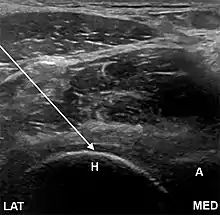

- The anterior longitudinal approach: the probe is aligned along the long axis of the femoral neck. The needle is introduced from an anteroinferior approach and is passed into the anterior joint recess at the femoral head-neck junction.

- The anterolateral approach, with the ultrasound probe oriented axially and the femoral head and acetabular rim in view. This often shortens the distance from needle skin entry to joint compared to the longitudinal approach making it a useful approach in larger patients. The introduced needle remains lateral to the femoral neurovascular bundle, and the needle is advanced until its tip rests on the femoral head.